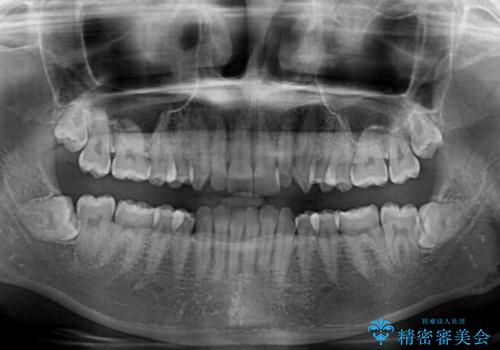

- 前歯のデコボコとディープバイトを気にして来院された患者様です。

左上前歯前方に飛び出しているため、歯列全体が前方に移動している状態でした。

短期間で確実に仕上げたいとのことで、アンカースクリューと補助装置を併用して歯列の後方移動を図り、ワイヤー装置にて矯正治療を行うこととしました。